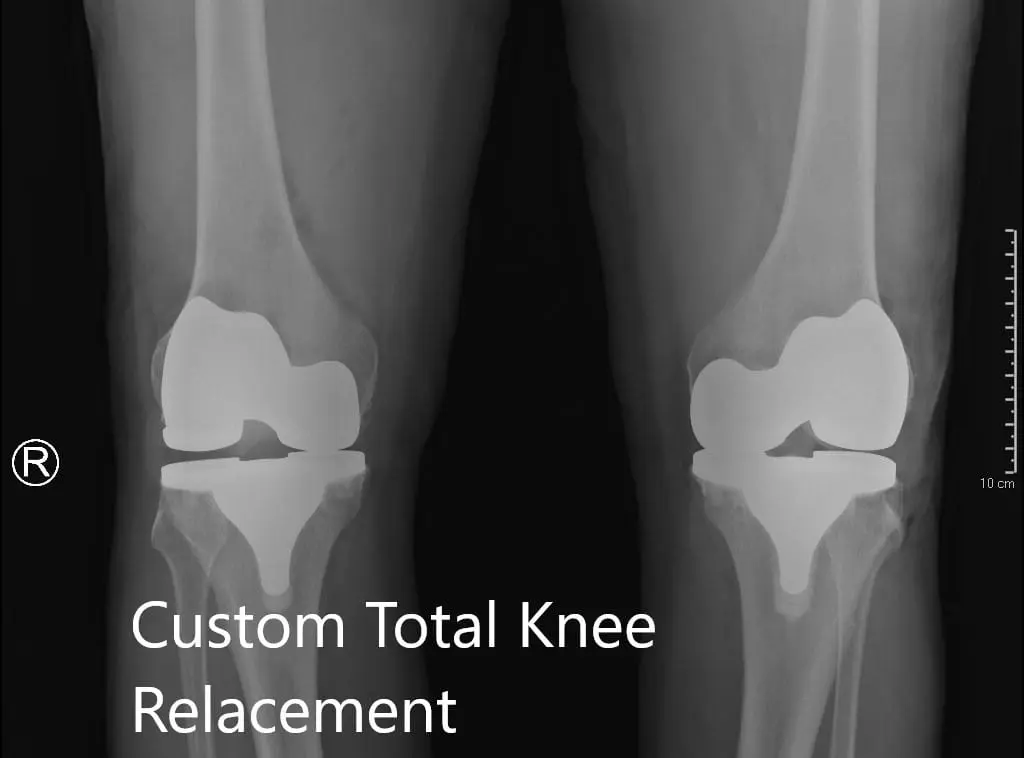

Her imaging studies of both the knee revealed severe tricompartmental osteoarthritis. Considering her lifestyle limiting knee pain, she was advised bilateral custom total knee replacement. Risks, benefits, and alternatives were discussed with the patient at length. She agreed to go ahead with a bilateral custom knee replacement.

Postoperative X-ray showing the lateral views of both knees

Postoperative X-ray showing the lateral views of both knees.

Postoperative X-ray showing the AP view of both knees

Postoperative X-ray showing the AP view of both knees.